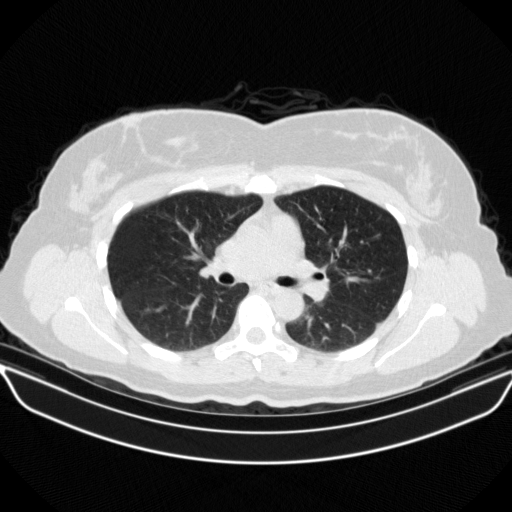

Reconstructed NATIVE CT scan (cycle consistency)

Full window (WL 1023.5, WW 4095 β†’ Low βˆ’1024, High +3071)

Actual HU range: [-1024.0, 1467.2]

Lung window (WL -600, WW 1500 β†’ Low βˆ’1350, High +150)

Actual HU range: [-1123.5, 150.0]

Mediastinum window (WL 40, WW 400 β†’ Low βˆ’160, High +240)

Actual HU range: [-160.0, 240.0]